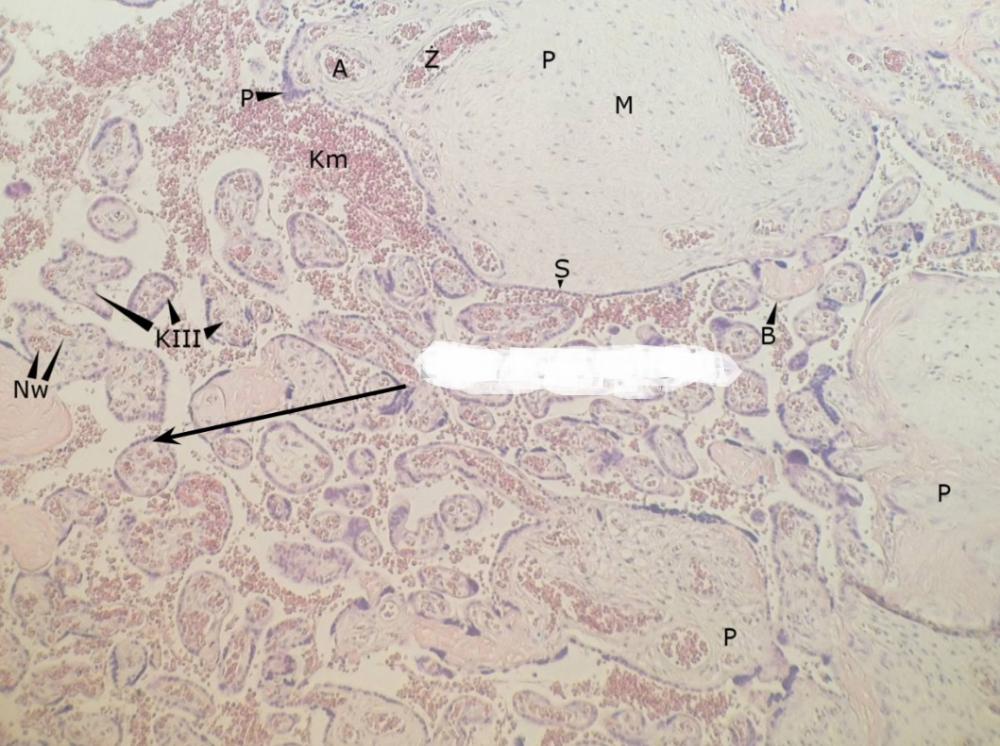

pnie kosmówkowe (łożysko, płyta kosmówkowa)

kosmki końcowe (łożysko, płyta kosmówkowa)

syncytiotrofoblast (łożysko, płyta kosmówkowa)

węzły syncytiotrofoblastu - jądra komórkowe (łożysko, płyta kosmówkowa)

płytki nabłonkowo-naczyniowe - cytoplazma bez jąder (łożysko, płyta kosmówkowa)

erytrocyty matki (łożysko, płyta kosmówkowa)

erytrocyty płodu (łożysko, płyta kosmówkowa)

przegroda łożyskowa (łożysko, płyta kosmówkowa)

komórki doczesnowe (łożysko, płyta kosmówkowa)

komórki kotwiczące (łożysko, płyta kosmówkowa)

naczynia włosowate (łożysko, płyta kosmówkowa)